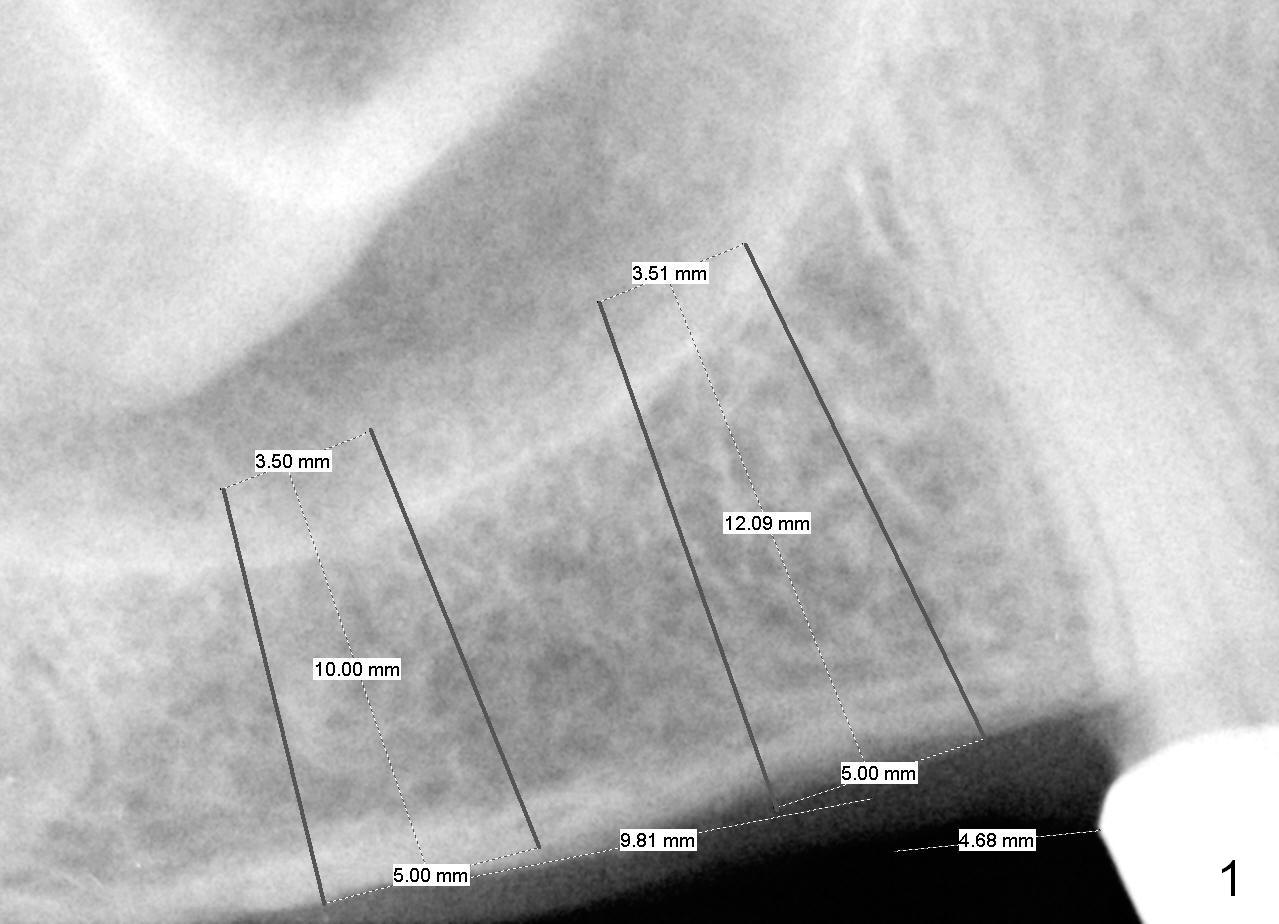

Initial osteotomy will be 10 mm. If the bone feels soft while 2 mm pilot drilling, use bone expanders until 2 sizes smaller than 5 mm SM implant (notice the apical diameter). Eventually use bone graft to lift the sinus floor. If the bone is not soft, use DIO burs in a slow speed to see whether autogenous bone can be collected or not.

Both the teeth #30 and 31 are supraerupted. There is no restorative space for #2. So #3 implant will support the most distal crown. A 4 mm tissue punch is used, followed by a 2 mm pilot drill. Bone type is 3. A parallel pin shows that the trajectory needs to be adjusted (Fig.2). By the time a 4.5 mm tap is placed, the trajectory is within normal limit (Fig.3,4 T). A 5.3x10 mm implant is placed with insertion torque > 60 Ncm (Fig.5; *: sinus lift). After insertion of an abutment, an immediate provisional is fabricated with intention to prevent further supraeruption of the tooth #30 during #3 implant osteointegration.